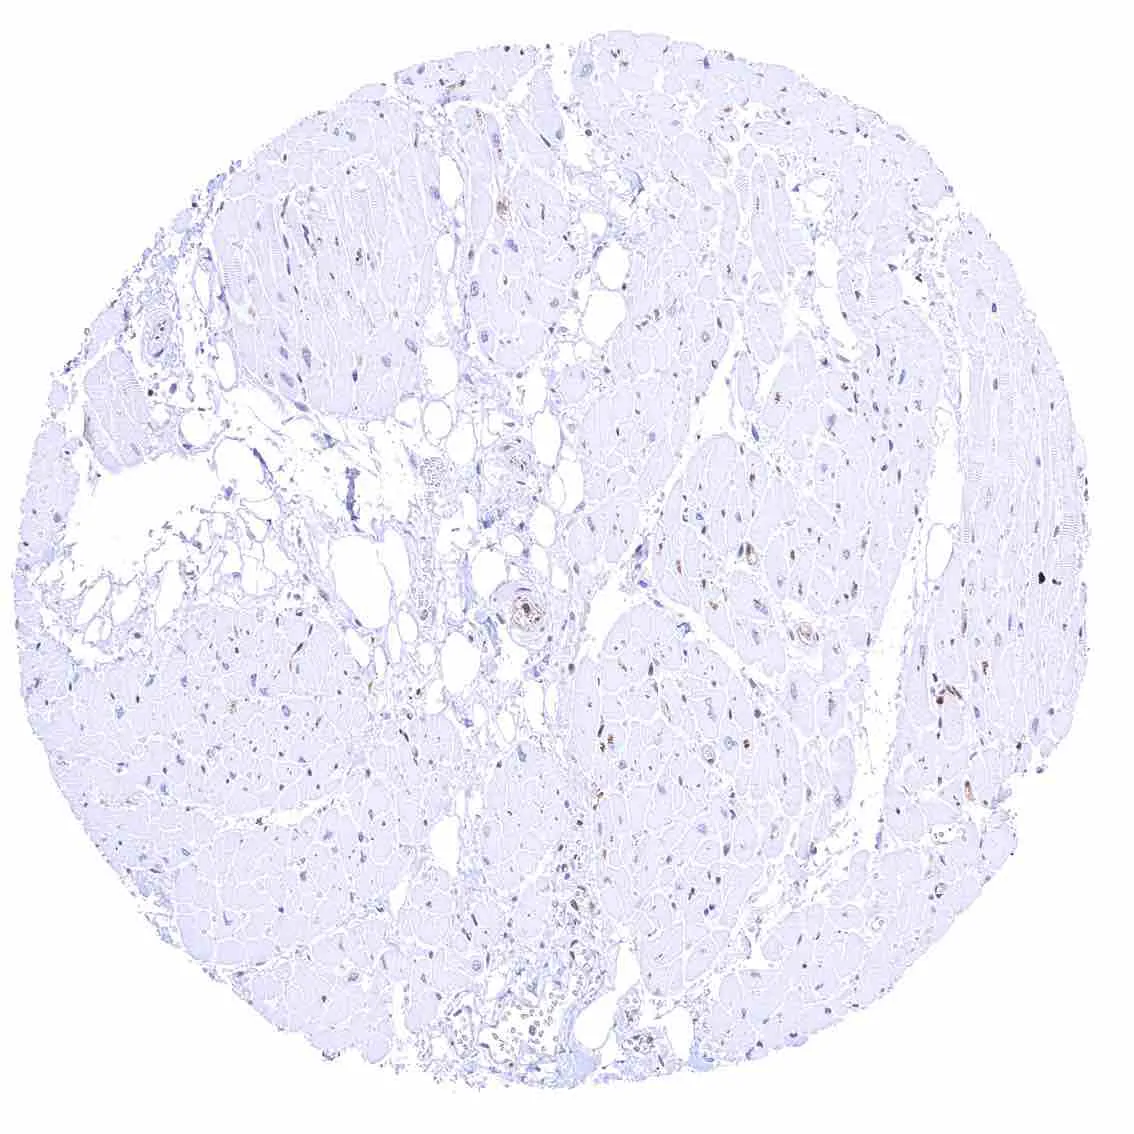

Bone marrow – The number of p27 positive cells is rather low.